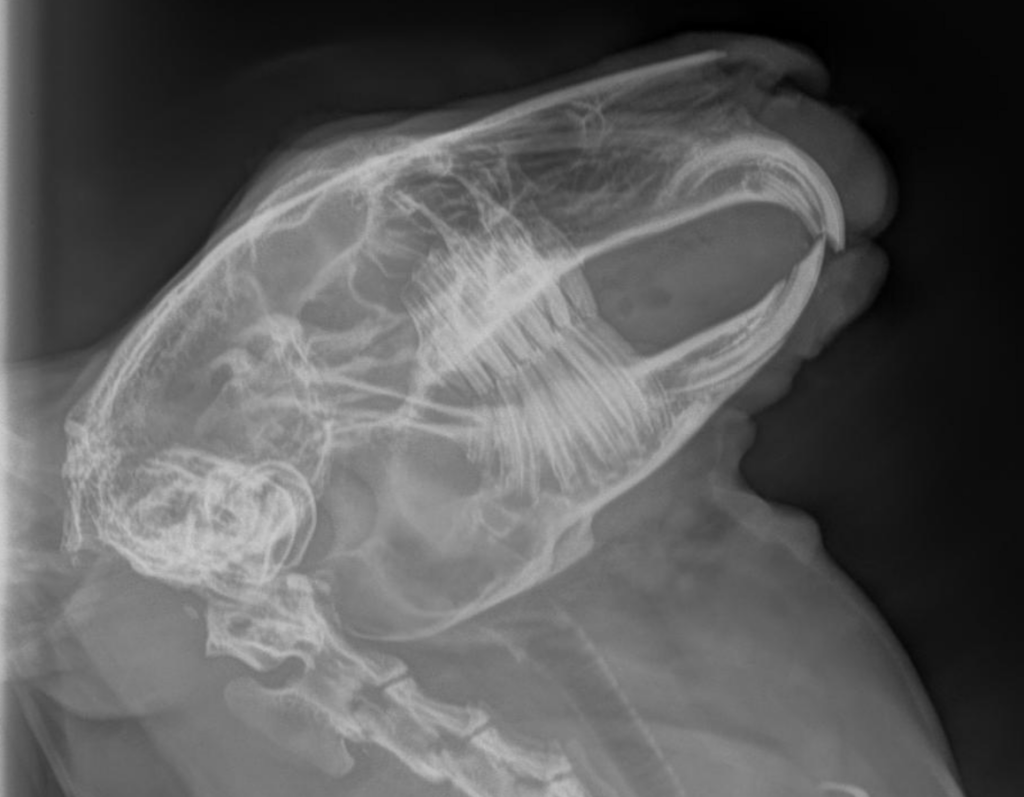

Une radiographie des bulles tympaniques a été réalisée afin d’exclure une otite moyenne ou interne.

À la radiographie, aucune anomalie évidente n’a été détectée.

Cependant, n'étant pas habitué à l'interprétation des clichés radiographiques chez le lapin, un avis spécialisé serait précieux.

Sur vos radiographies, les bulles tympaniques apparaissent symétriques, bien aérées, sans épaississement ni lyse de leur paroi. Le reste des structures crâniennes semble normal. Il n’y a donc pas d’indication radiographique d’otite. Un scanner permettrait de confirmer cette évaluation, mais si les propriétaires ont des contraintes financières, le traitement empirique recommandé par Dr. Mentré semble approprié.